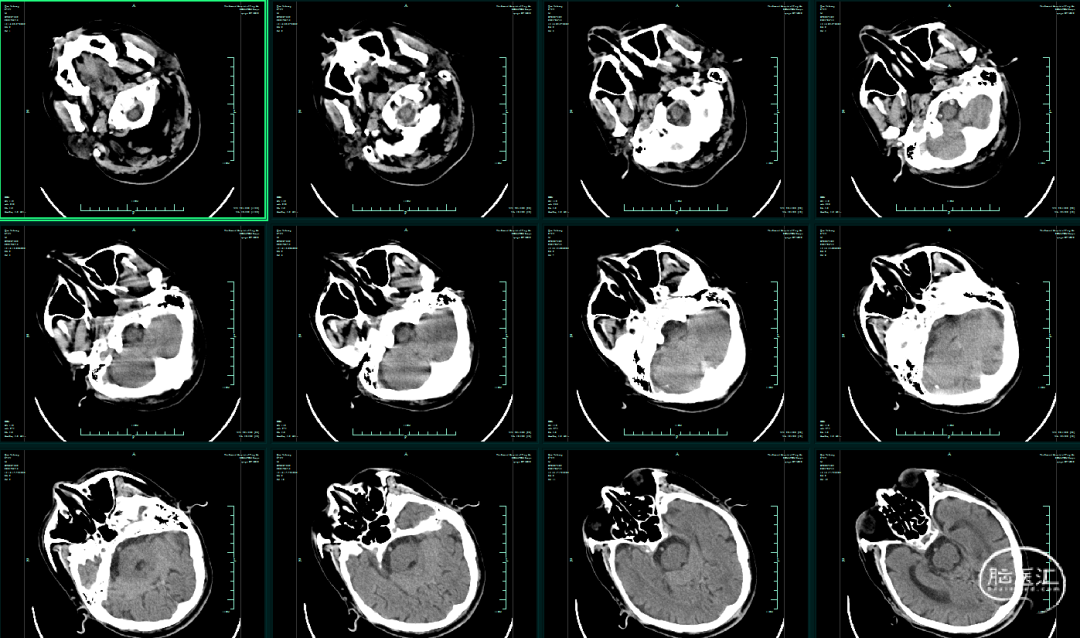

影像学资料

CT平扫未见颅内出血,右侧大脑中动脉高密度影,可疑血栓。